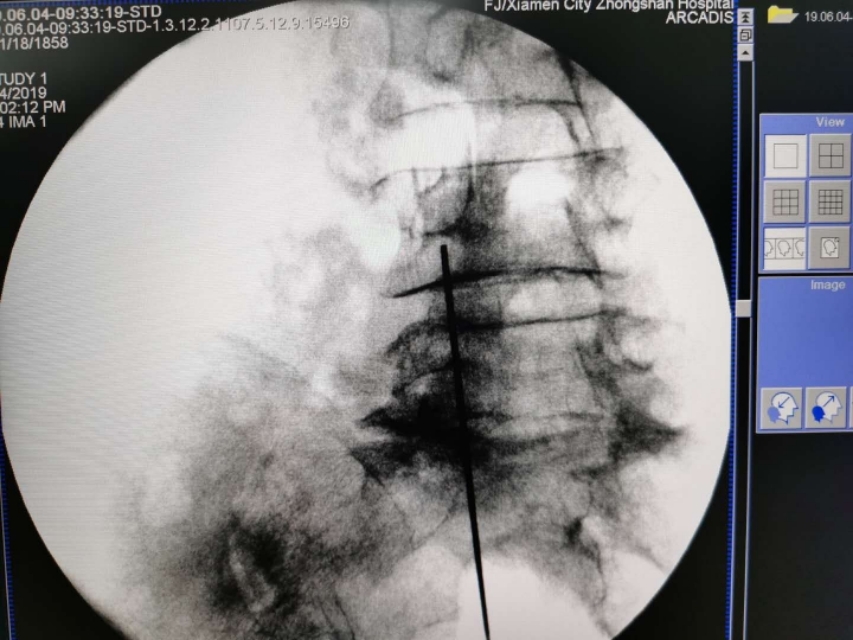

C臂透视左侧斜位片。腰4、腰5骶1左侧附件成苏格兰犬状。确定进针点。

在C臂辅助下穿刺针顺利到达目标靶点safety triangle

询问患者下肢没有异常。回抽证实处于安全区。遂注入药物。